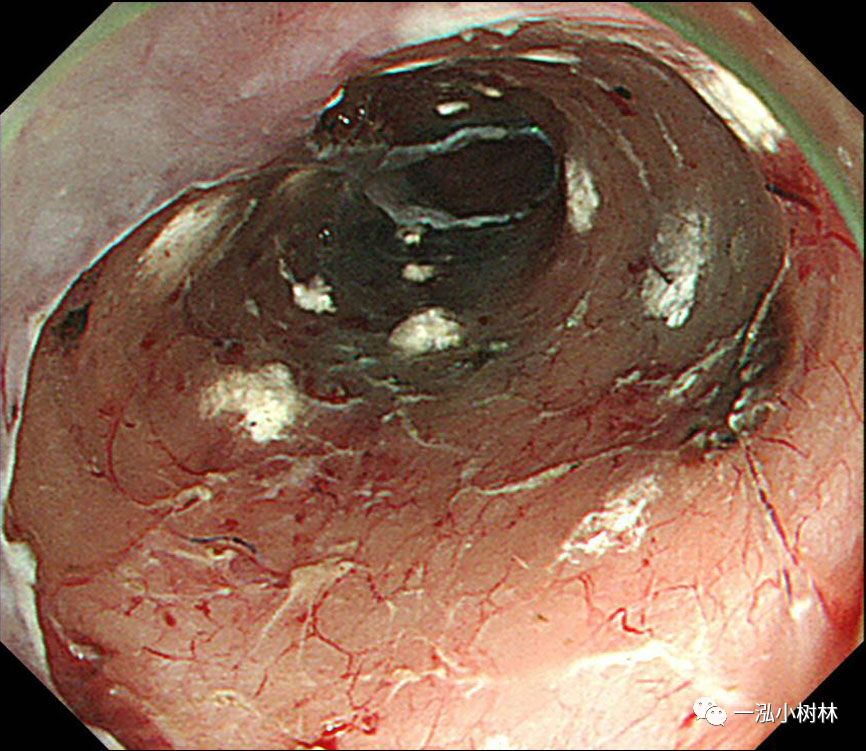

图11 黏膜整块切除